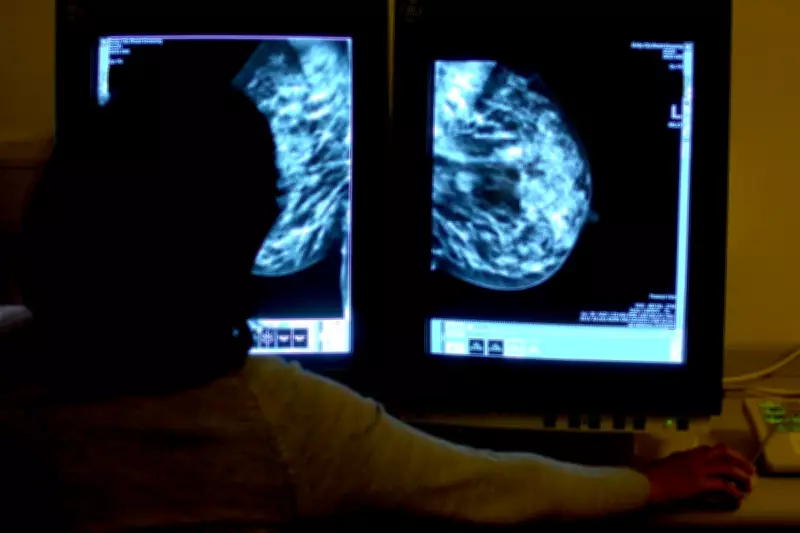

Artificial intelligence (AI) can identify early indicators of heart disease during routine breast cancer screenings, according to groundbreaking new research. Experts have leveraged AI technology to detect calcification in breast arteries from standard mammograms, a substance strongly linked to an increased risk of heart attack, stroke, and premature death.

The integration of AI into existing breast cancer screening programmes offers a promising solution to address the persistent issue of underdiagnosis in women's heart health. By utilising AI to analyse mammograms, healthcare providers could uncover undiagnosed heart conditions in thousands of individuals, potentially saving lives through early detection. This approach not only enhances the value of routine screenings but also requires no additional infrastructure, making it a cost-effective addition to national mammography initiatives.